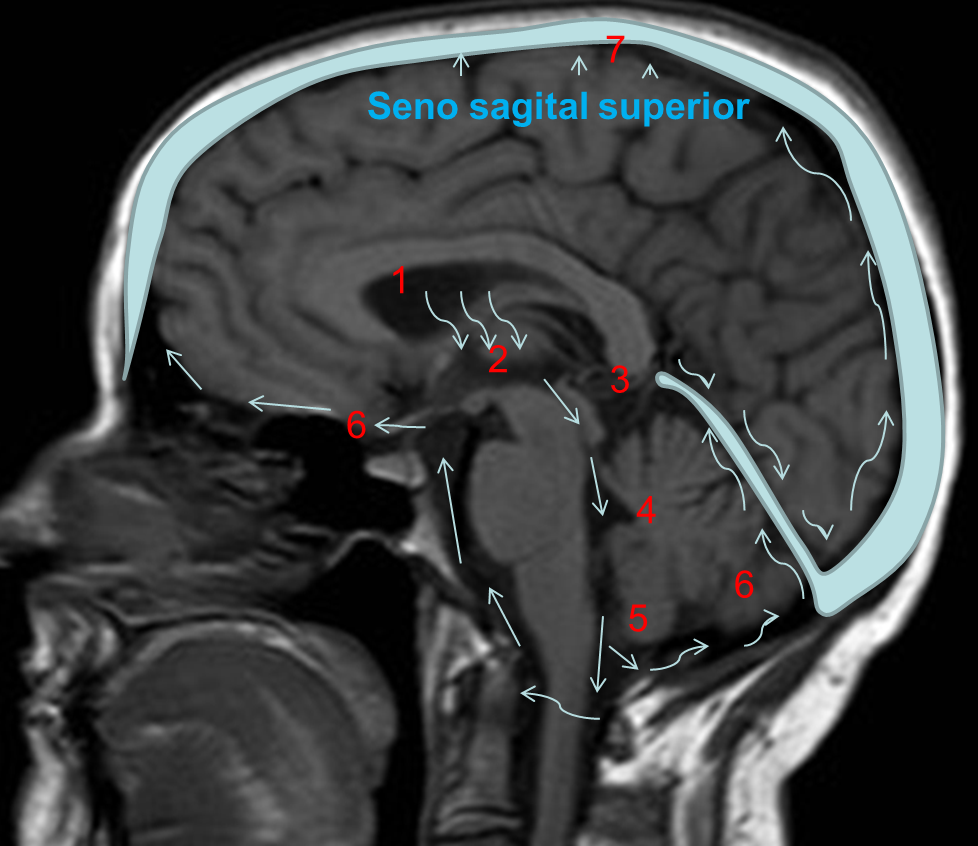

En la Imagen 1 muestro la localización normal de las estructuras cerebrales que van a estar alteradas en nuestro caso:

En la Imagen 2. podemos ver la circulación habitual del LCR. El líquido cefalorraquídeo (LCR) se produce de forma continua en los plexos coroideos que están situados fundamentalmente en los ventrículos laterales 1 (también en el III y IV ventrículo), posteriormente pasa al III ventrículo 2, después por el Acueducto de Silvio 3 pasa al IV ventrículo 4, y de ahí al espacio subaracnoideo 5 y 6 donde se dirige hacia la convexidad cerebral para reabsorberse en las granulaciones aracnoideas y pasar al sistema venoso por medio del seno venoso sagital superior 7.